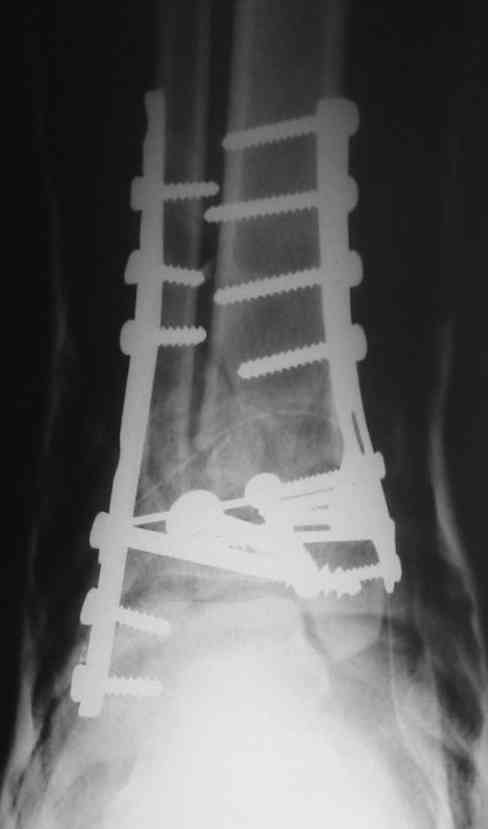

OK, Dr Driagin, Ja operiroval bolnogo po Vashemu, hotia sam ni ochen' ubezden' v itom, t.k. bolnoi otkazalsa na proch' ot ex.fix, ja emu sdelal ORIF + Kostnia plastika, snimky prelogiottsa,

Очень прилично получилось, но мне показалось, что винты на 4,5 мм.Это принципиально винты используются 3,5 и 4,0 мм. И проекцию прямую бы переделать. С уважением Дрягин

На представленном снимке видно, что эпифиз смещен латерально.

Сейчас с этим ничего не сделать, похоже.

Пластина лист клевера есть в варианте DCP -динамическая компрессирующая пластина.В ней все отверстия круглые,развальцованные отверстия под винт 3,5, чтобы шляпка винта не торчала.Винты 4,5 тоже проходят в эти отверстия, но шляпка не погружается.Могут быть проблемы с мягкими тканями.Пластина LCP -пластина с блокированием.В каждом отверстие пластины нарезана резьба и на шляпке винта такая же.Получается блок винт-пластина-кость.Очень крепко.Первоначально она готовилась для остеопороза, много лет в Давосе её разрабатывали.Я видел там первые образцы ещё в 1995 году, а начали они в 80-годах.Насчёт оси по рентгенограмме пока не согласен пусть сделают хорошую, правильную прямую проекцию.С уважением Дрягин

Однозначно сказать сложно.Расстояние между тараном и медиальной лодыжкой меньше чем между тараном и крышей большеберцовой кости.Это может быть за счёт не правильной укладки.Пока не отчаиваетесь.Главное вы поняли принцип.Сделайте несколько проекций прямых и посмотрим.Для всех интересно.С уважением

Мне кажется, что все конечно далеко от идеала. Сложный перелом. Есть ощущение, что малоберцовая кость (ключ!) фиксирована с ротацией и удлинением. Снимки конечно необходимо сделать в правильных проекциях и без гипса...

Применение шурурпов 4.5 мм и более толстых пластин крайне недопустимы. Рекомендуется низкопрофильные, контурированные пластины с шурупами 3.5 мм, а иногда те же 3.5 шурупы но с головкой 2.7 мм.